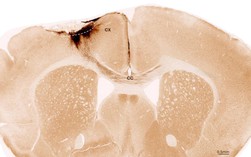

Trường hợp đầu tiên, ông N.V.T. (70 tuổi, ngụ Phú Quốc) được đưa vào TTYT Phú Quốc sáng 2-10 trong tình trạng lơ mơ, liệt nửa người trái, chỉ số thang điểm đánh giá đột quỵ (NIHSS) 18 điểm. Sau khi hội chẩn khẩn với các bác sĩ Bệnh viện Chợ Rẫy đang trực hỗ trợ tại đây, bệnh nhân được kích hoạt quy trình đột quỵ, chụp CT và tiêm thuốc tiêu sợi huyết.

Dù có cải thiện nhưng bệnh nhân hồi phục chậm do nghi ngờ tắc mạch máu lớn và được chuyển tiếp về Bệnh viện Chợ Rẫy điều trị chuyên sâu. Sau 5 ngày, bệnh nhân ổn định và được chuyển về địa phương phục hồi chức năng.

Trường hợp thứ hai, ông L.V.Q. (49 tuổi, ngụ Phú Quốc) nhập viện chiều 3-10 với triệu chứng yếu nửa người trái, nói đớ, NIHSS 5 điểm. Sau hội chẩn và can thiệp tiêu sợi huyết, bệnh nhân phục hồi thần tốc chỉ sau 18 giờ, chỉ số NIHSS về 0 và đã xuất viện.

Theo BS Việt, đây là 2 ca đột quỵ đầu tiên được xử trí thành công tại TTYT Phú Quốc nhờ quy trình điều trị chuẩn và phối hợp chặt chẽ với đội ngũ chuyên môn của Bệnh viện Chợ Rẫy. Dù dùng cùng phương pháp tiêu sợi huyết, kết quả 2 bệnh nhân khác nhau do nhiều yếu tố, trong đó có liên quan đến tắc mạch lớn và tình trạng mạch máu nền.